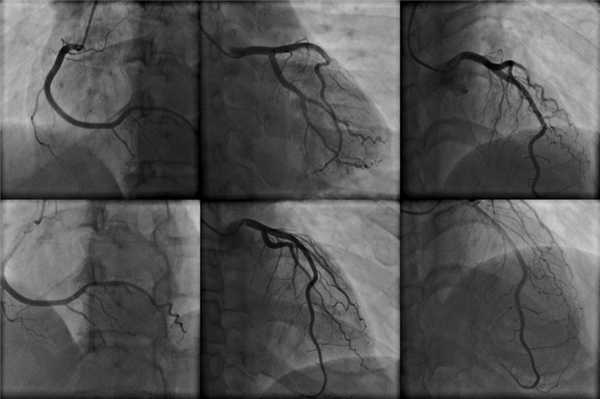

Нередко катетеризацию сердца проводят с целью проведения коронарографии.

Во время катетеризации сердца могут проводиться такие методики обследования:

- ангиография - для визуализации камер сердца, коронарных сосудов, легочных артерий и аорты;